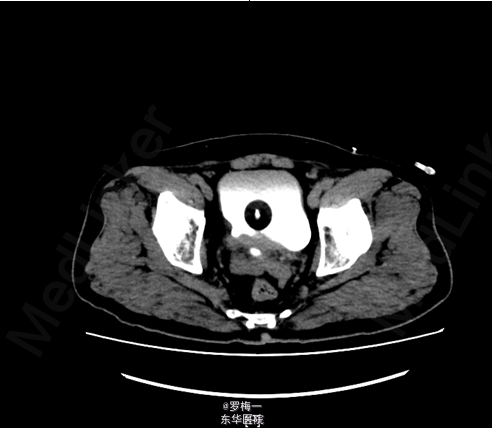

住院后完善相关检查,PSA两项均升高,其他各项术前常规检查未见明确手术禁忌证。遂于2015-04-02行经直肠前列腺穿刺活检,病理提示“符合前列腺增生伴慢性炎”。盆腔MR平扫+增强扫描考虑膀胱癌复发可能性大;彩超肝胆胰脾及核素骨扫描暂未见肿瘤远处转移证据。